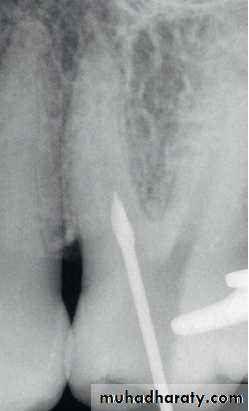

Gates-Glidden DrillsGates-Glidden drills are suited for straight-line access modification. A No. 2 Gates (approximately size No. 70) is often used first, followed by the No. 3 (approximately size No. 90) and perhaps the No. 4 (approximately size No. 110). In very narrow canals, a No. 1 Gates (approximately size No. 50) may be needed. It is important to remember the size of the Gates-Glidden drills. If the canal orifice cannot accommodate a No. 50 file, careful hand instrumentation should be performed to provide adequate initial coronal space; alternatively, a tapered NiTi orifice shaper may be used in such a case. To prevent stripping perforations, Gates-Glidden drills should not be placed apical to canal curvatures (Figure1).

Figure (1): Gates-Glidden use in coronal portion of root preparation.